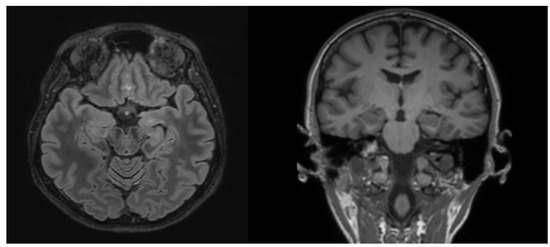

GAD65 Antibody-Associated Epilepsy

Autoimmune processes are an increasingly recognized cause of seizures. Antibodies against neuronal surface antigens are implicated in the development of acute symptomatic seizures secondary to autoimmune encephalitis, whereas antibodies against intracellular antigens (anti-glutamic acid decarboxylase (GAD) and onconeural antibodies) are found in cases [...] Read more.

Autoimmune processes are an increasingly recognized cause of seizures. Antibodies against neuronal surface antigens are implicated in the development of acute symptomatic seizures secondary to autoimmune encephalitis, whereas antibodies against intracellular antigens (anti-glutamic acid decarboxylase (GAD) and onconeural antibodies) are found in cases of autoimmune-associated epilepsy (AAE). AAE is described as isolated drug-resistant epilepsy without any specific magnetic resonance imaging (MRI) or cerebrospinal fluid changes and with a very limited response to immunotherapy. We present a clinical case and a literature review on autoimmune-associated epilepsy to increase awareness of this disease and illustrate its complexity. This is a clinical case of a female with a history of refractory focal epilepsy. The patient had been given several trials of multiple antiepileptic drugs and their combinations without any clear effect. Multiple evaluations including brain MRI, PET, and interictal and ictal electroencephalograms were performed. An APE2 score was calculated with a result of 4 and, in the presence of anti-GAD65 antibodies in the serum, the diagnosis of AAE was confirmed. There was no effect after five sessions of plasma exchange; however, after a course of intravenous immunoglobulin, a positive but temporary clinical effect was noticed: anti-GAD65 levels initially decreased but rebounded to previous levels 6 months later. Full article